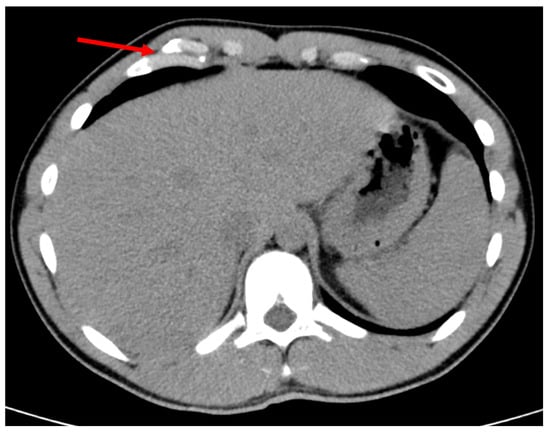

Figure 1.

Malunion fracture of the costal margin. Red arrow points to the location of injury.